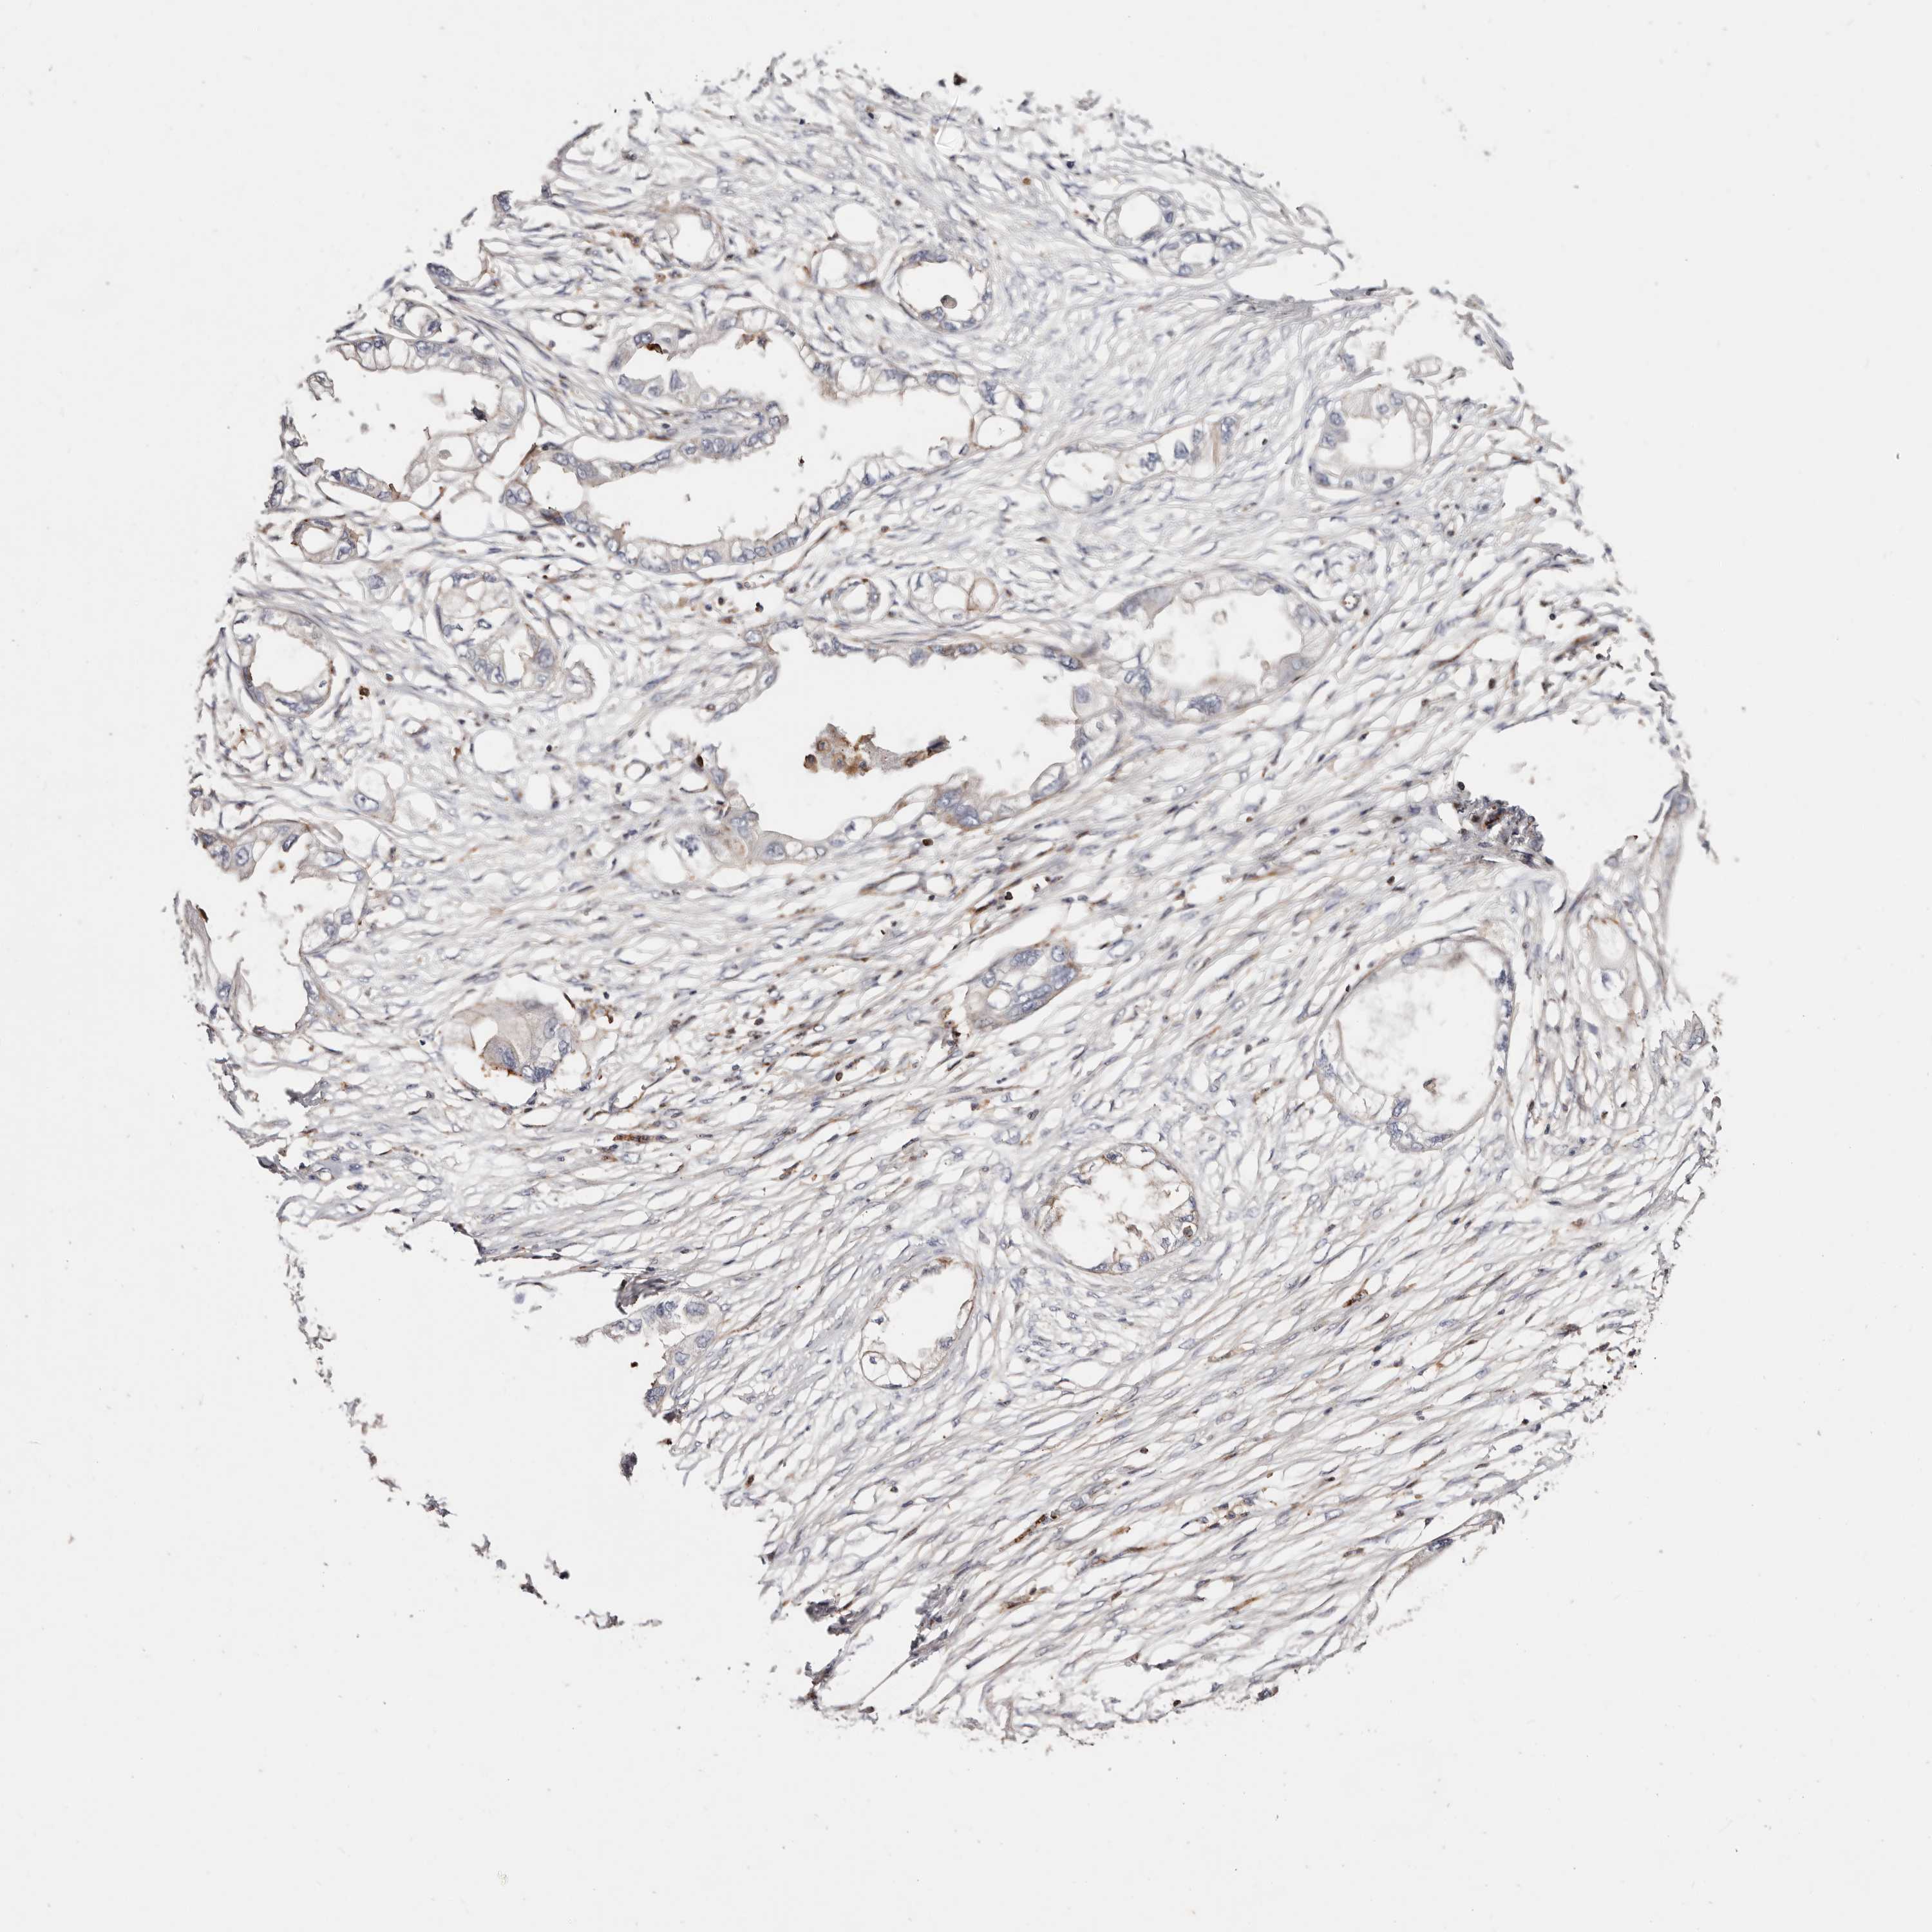

ENDOMETRIAL CANCER - Protein expressioni

A mouse-over function shows sample information and annotation data. Click on an image to view it in a full screen mode. Samples can be filtered based on level of antibody staining by selecting one or several of the following categories: high, medium, low and not detected. The assay and annotation is described here.

Note that samples used for immunohistochemistry by the Human Protein Atlas do not correspond to samples in the TCGA dataset.

Antibody stainingi

Antibody staining in the annotated cell types in the current human tissue is reported as not detected, low, medium, or high, based on conventional immunohistochemistry profiling in selected tissues. This score is based on the combination of the staining intensity and fraction of stained cells.

Each image is clickable and will lead to virtual microscopy that enables deeper exploration of all samples and also displays staining intensity scores, fraction scores and subcellular localization as well as patient and tissue information for each sample.

Antibody HPA004912

Antibody HPA013350

Antibody CAB012209

Staining

High

Medium

Low

Not detected

Intensity

Strong

Moderate

Weak

Negative

Quantity

>75%

75%-25%

<25%

None

Location

Nuclear

Cytoplasmic/membranous

Cytoplasmic/membranous,nuclear

Adenocarcinoma, NOS

Adenocarcinoma, metastatic, NOS